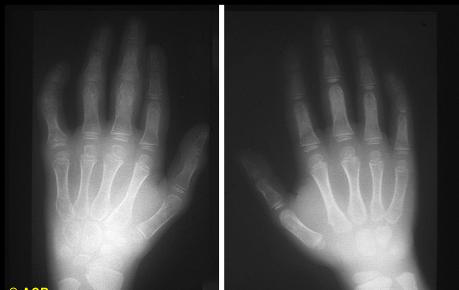

图2-3双手幼年型特发性关节炎

双手诸掌指及指间关节骨质疏松

左手腕骨及掌骨骨质疏松